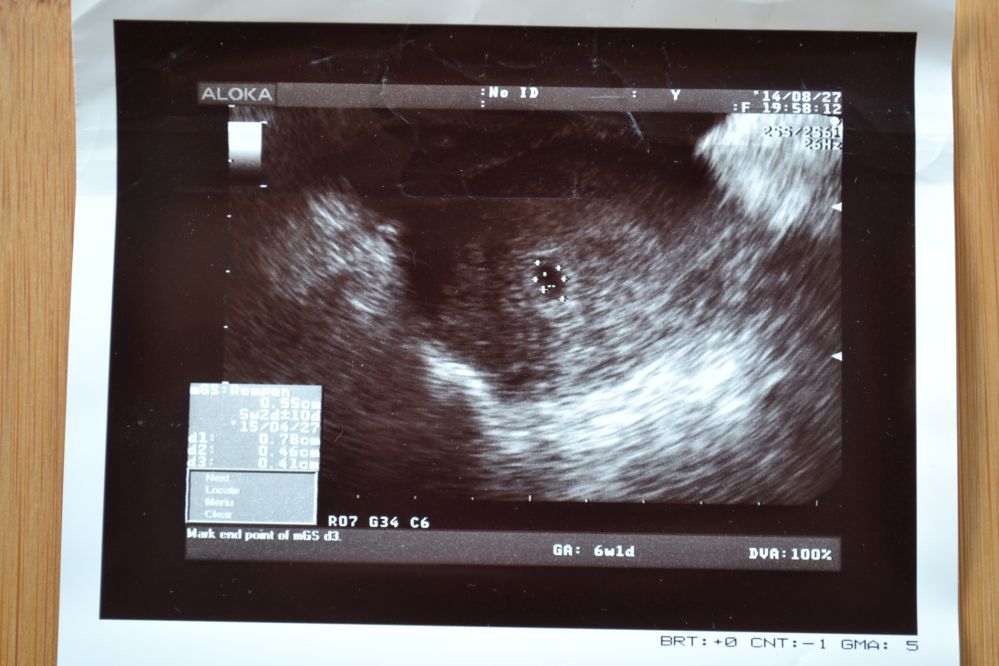

Jutro wkleję dwa zaległe zdjęcia i może trzecie świeże